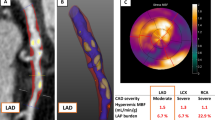

PET/CT image analysis. a Example of the SUV measurement in the left coronary artery. The red circles indicate ROIs of the same size, which are slid along the course of the vessel, indicated with black arrows. Within the ROIs the SUV and subsequently the TBR was calculated. Coronal PET image on the left shows no discernible FDG uptake in the myocardium. Axial CT images were used to localize the left coronary artery, and measurements of the SUV were then performed on the fused PET/CT images along the course of the left coronary artery. The SUVmax in this patient was 0.9 and the mean venous SUV was 1.0, resulting in a target to blood pool ratio of 0.9 (low tertile). b PET/CT images of a 77-year-old female patient with a history of hypercholesterolaemia and hypertension. Coronal PET image on the left shows a homogeneous FDG uptake in the myocardium, which hampers the measurements of the SUV. FDG uptake on the axial PET images is caused by the myocardium and not by the left coronary artery. Patients with myocardial FDG uptake were excluded from further analysis. c Examples of the calcified plaque (CP) scoring system [9]. Images from left to right, score of “0”, no calcified plaque; score of “1”, CP covered less than 10% of the vessel circumference; score of “2”, CP involved 10–25% of the vessel circumference; score of “3”, 25–50% of the vessel circumference; and score of “4”, more than 50% of the vessel circumference involved

Plaque burden

The CT scans were examined for the presence of calcified plaque (CP) in the walls of the right and left common carotid artery, ascending aorta, aortic arch, descending aorta, abdominal aorta and both iliac arteries. A cut-off value of 130 HU was used for the identification of calcification. The amount of calcification was semi-quantitatively determined according to the following scale [11]: A score of “0” was assigned when CPs were absent, “1” was assigned when a single, small CP was found, encompassing less than 10% of the vessel circumference, a score of “2” was assigned if the CP involved 10–25% of the vessel circumference, “3” if 25–50% and “4” if >50% of the vessel circumference was involved (see Fig. 1c). The total CPB was calculated as the sum of the CP values in the eight vessels listed above.